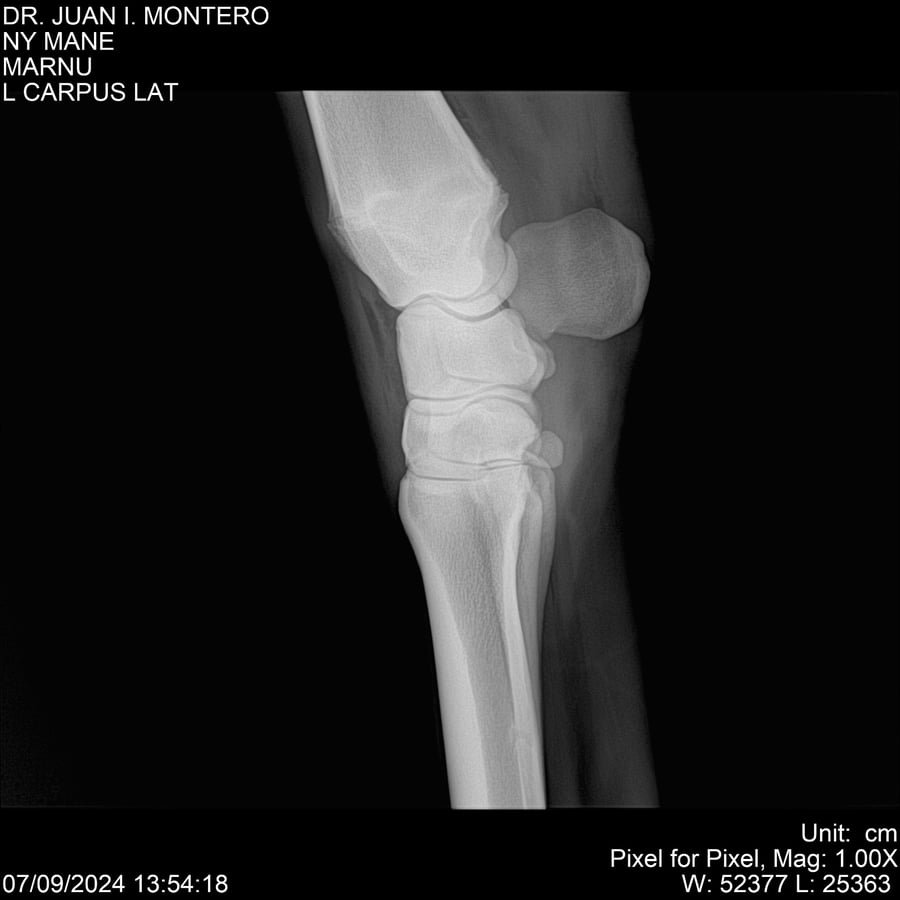

LOTE 20, NY MANE Lote Anterior Volver al remate Lote Siguiente Ficha Contacto Montevideo - Ficha del Lote Identificador: #282520 Categoría: Yeguarizos 76 Visualizaciones ClicData Contacto Empresa: Abelenda N. R., Walter Hugo Nombre*: Teléfono* : E-mail* : Mensaje Enviar Registrese gratis Este contenido Exclusivo está disponible sólo para usuarios registrados Ingresar